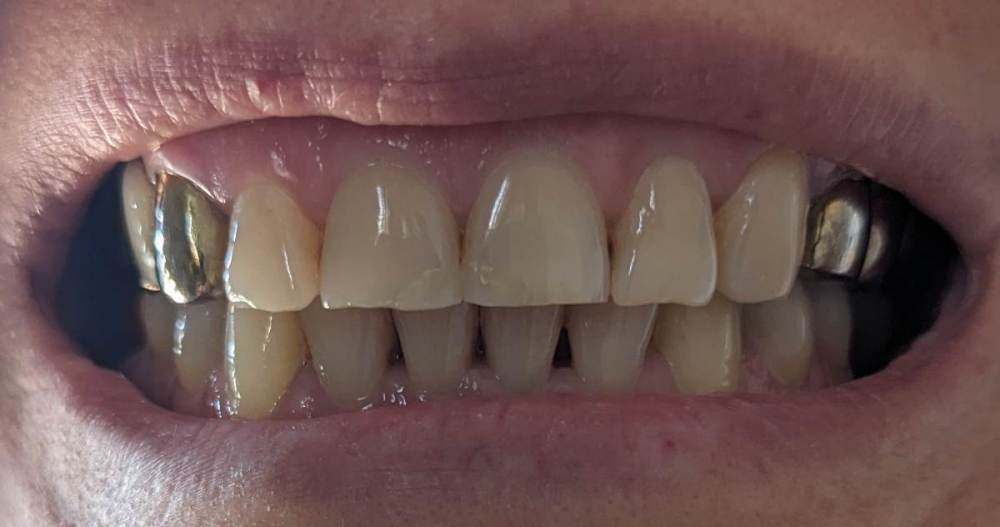

после сильного стресса нарушился прикус. на верхней челюсти боковые зубы сдвинулись вовнутрь, а передние ушли немного вперёд.

в детстве были полностью вырваны 4 и 5 зубы справа, и 6 слева. на боковых зубах справа и слева стоят рандолевые мосты - по четыре жевательных зуба (справа 3, 4, 5, 6 зубы. слева - 4 это отдельная коронка, а 5, 6, 7 - мост). хочу поменять эти мосты на металлокерамические. и есть желание выровнять кривой зуб (2 справа).

врач, который ставит коронки, говорит что новые мосты полностью исправят прикус, но есть сомнения, ведь передние зубы мосты не затронут.

вопрос - можно ли будет исправить прикус после замены старых железных мостов на металлокерамические ?

если да, то чем лучше - брекетами или капой ? или всё-таки лучше начать с ортодонта и исправления прикуса, а мосты поставить после